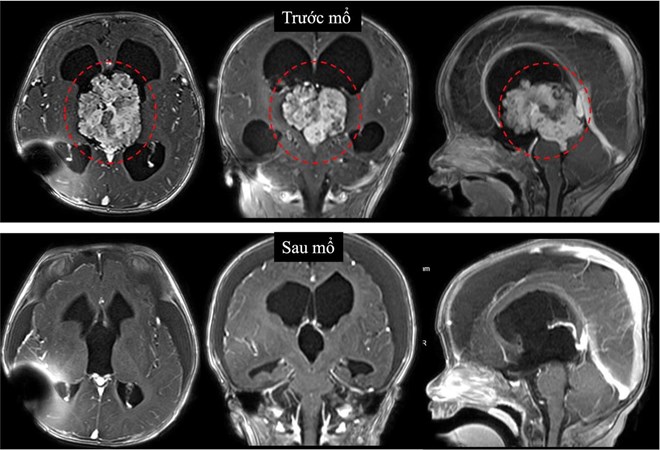

Kết quả chụp cộng hưởng từ sọ não cho thấy khối u tại não thất III gây chèn ép dẫn đến não úng thủy tắc nghẽn. Đây là vị trí sâu, xung quanh có nhiều cấu trúc thần kinh quan trọng nên việc can thiệp phẫu thuật rất phức tạp. Kết quả giải phẫu bệnh xác định đây là u đám rối mạch mạc không điển hình độ 2, một dạng u hiếm của hệ thần kinh trung ương.

Tuy nhiên, sau 3 tháng, phim cộng hưởng từ cho thấy khối u phát triển nhanh, kích thước tăng hơn gấp 3 lần. Trước tình hình này, các bác sĩ đã tư vấn phẫu thuật sớm để kịp thời cứu trẻ.

TS.BS Trần Minh Huy - Khoa Ngoại Thần kinh, Bệnh viện Nhi đồng 1 - cho biết, đây là ca mổ khó do khối u nằm ở vị trí sâu, trung tâm não, xung quanh là nhiều cấu trúc thần kinh và mạch máu quan trọng. Khối u có kích thước lớn khoảng 6 cm, tăng sinh mạch nuôi, phát triển trong lòng não thất III, gây nhiều thách thức cho phẫu thuật viên. Bên cạnh đó, thời gian mổ kéo dài và nguy cơ mất máu cao ở bệnh nhi 7 tháng tuổi đòi hỏi trình độ chuyên môn cao và sự phối hợp liên chuyên khoa chặt chẽ.